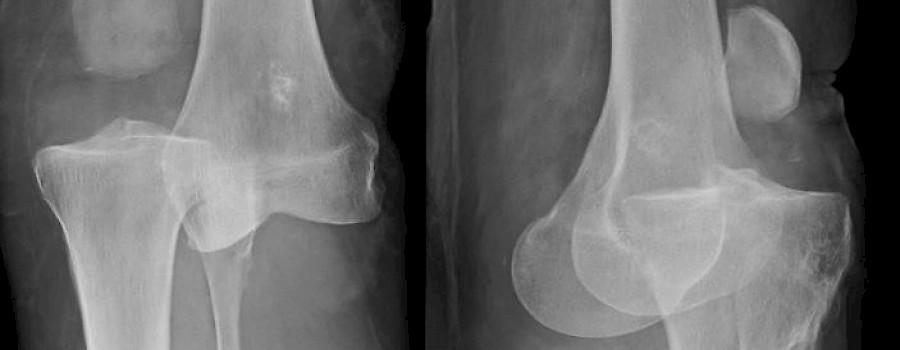

Der Nuklearunfall von Samut Prakan geschah im Februar 2000 in Thailand. Durch die Freisetzung von ionisierender Strahlung aus einem ausgedienten medizinischen Kobalt-60-Bestrahlungsgerät kamen dabei mindestens drei Menschen zu Tode...